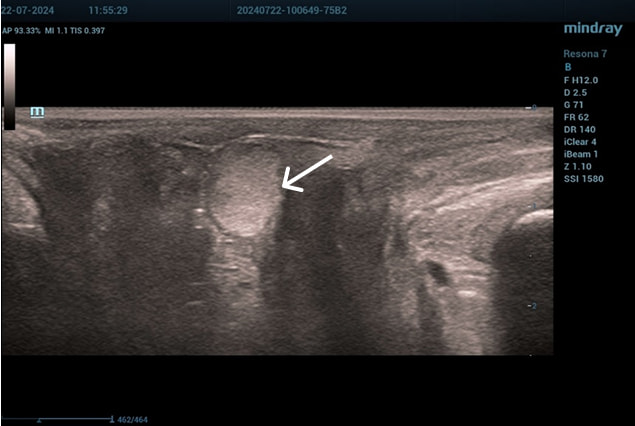

Эхограммы периуретральной области

Трансперинеальный доступ, конвексный датчик.

Слева от уретры округлое образование с четкой капсулой и мелкодисперсной взвесью размерами 1,5×1,0 см (филлер с воспалением), справа — анэхогенное овоидное образование (филлер).

Эхограмма 3